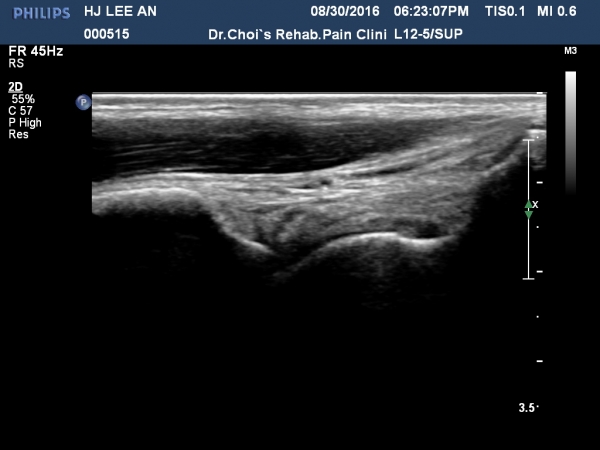

¹ß¸ñ ¾ÕÂÊ Á¾´Ü¸é°Ë»ç¿¡¼­ °üÀý³» ¼ö¾×Àú·ù´Â ¶Ñ·ÈÇÏÁö ¾ÊÀ¸³ª °æ°ñ °Å°ñ Á¢Ã˺ο¡ ¼Ò·®ÀÇ

¼ö¾×Àú·ù°¡ °üÂûµÊ(»çÁø 1, 2).